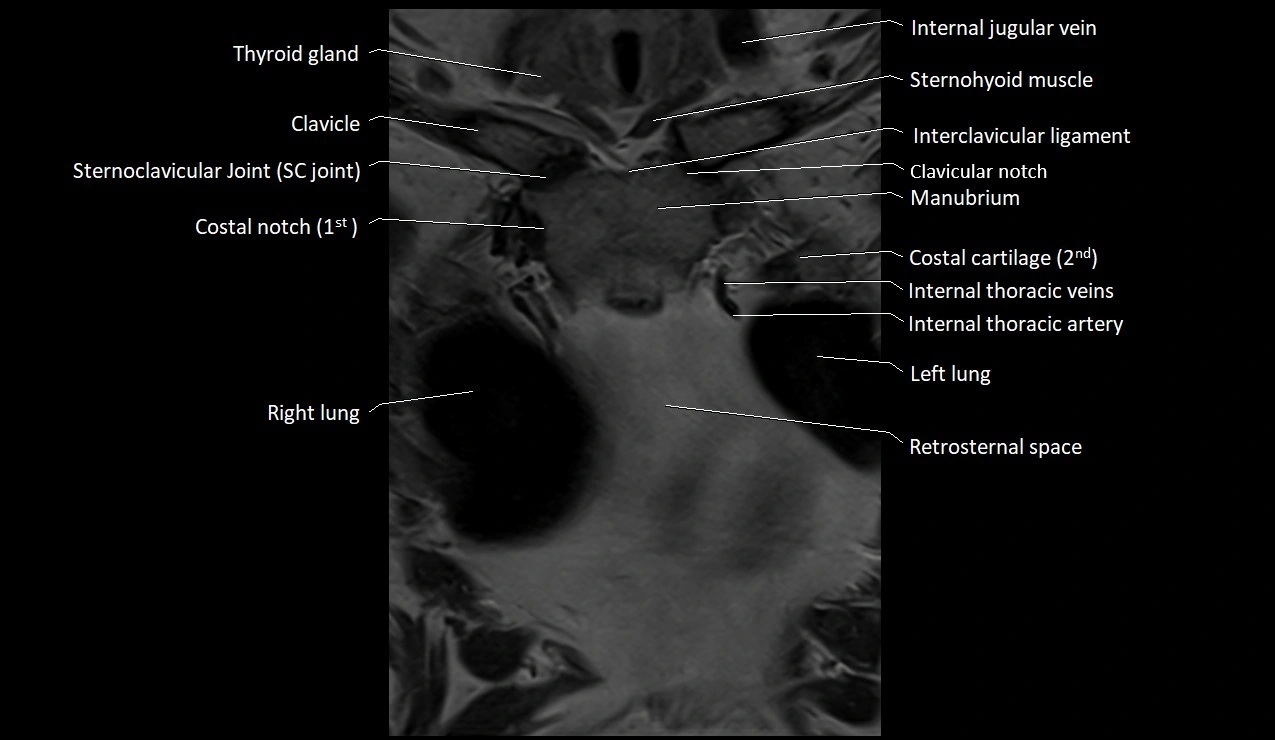

MRI images

image